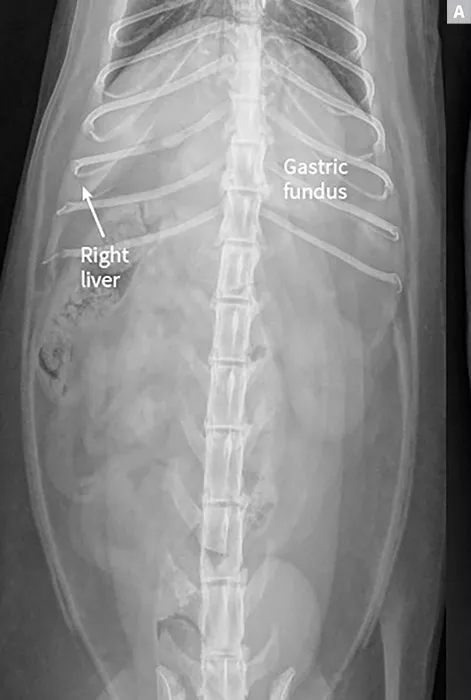

FIGURE 1A

Lateral radiographs of a clinically normal cat (A) and a 14-year-old neutered male domestic shorthair cat (B) presented with icterus and elevated liver enzymes. A normal feline liver should have a sharp, pointed margin (A; arrows) and should not extend past the costal arch; the gastric axis should be parallel to the ribs (A; line). The liver in the icteric cat extends past the costal arch, and has rounded borders (B; arrows). The stomach is displaced caudally (B; line; gastric axis from the fundus to the antrum). An ovoid mineralization (B; arrowheads) is also superimposed with the cranioventral liver in the location of the gallbladder. This cat was diagnosed with cholangitis, lipidosis, and a cholelith.